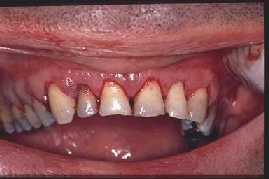

POST  OPERATORIO INMEDIATO

Images university of Sheffield DerWeb-project